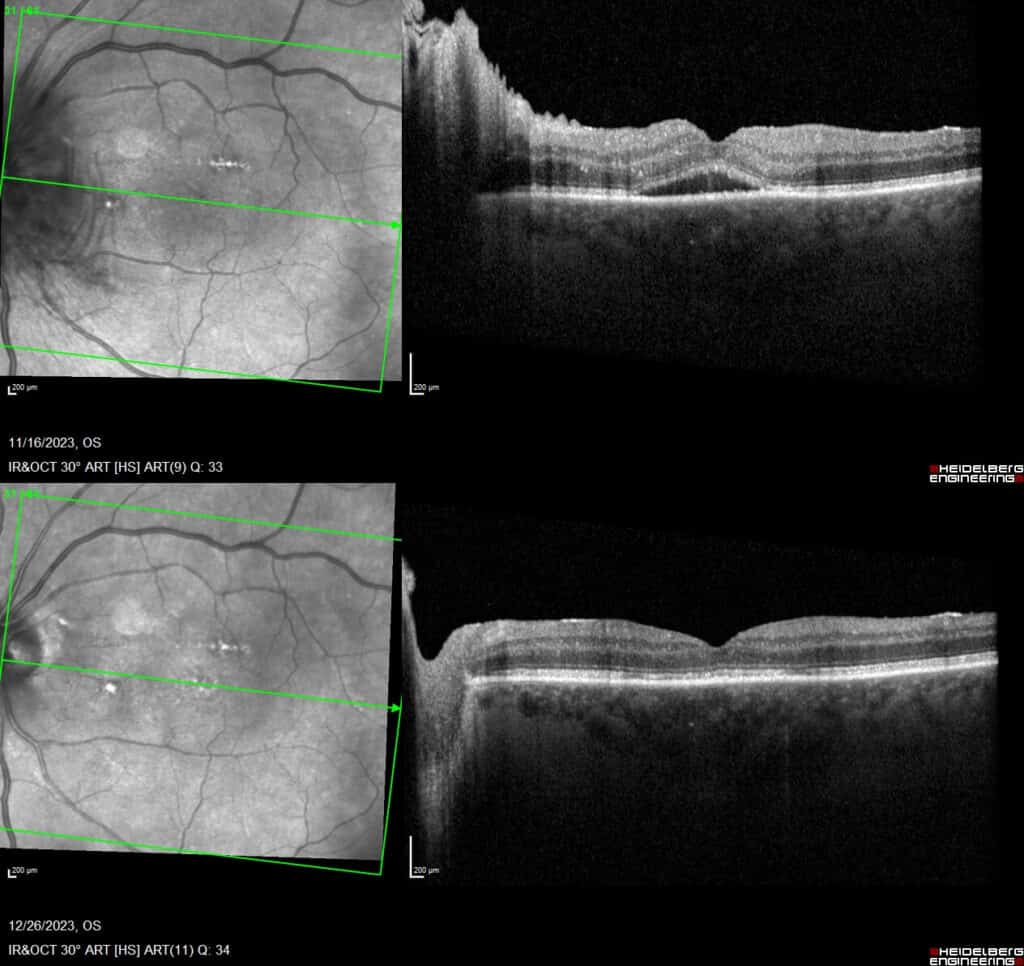

One month later, the left eye acuity worsened to 20/200 and there was a 1+ left afferent pupillary defect with markedly more disc edema to involve the nerve entirely (Figure 6). Over the course of multiple visits, the right optic nerve edema continued to improve leaving mild superior disc pallor with a final acuity of 20/25, dense inferior altitudinal field loss and significant nerve fiber layer thinning of the superior half of the nerve. The left optic nerve edema lessened at subsequent visits; the final acuity was 20/200 with overall peripheral loss and a 2+ left afferent pupillary defect. Interestingly, the left eye also developed subretinal fluid throughout the macula with residual outer retinal disruption which eventually resolved (Figure 7). Primary care and nephrology adjusted his hypertensive medications multiple times, which proved challenging given hypertensive episodes after medication reductions.

Figure 7. Macular OCT OS. (Top )Subretinal fluid within the macula. (Bottom) Resolved subretinal fluid with outer retinal disruption.

This case also highlights another unique presentation in the left eye – subretinal fluid in the macula region. Submacular fluid has been documented with NAION in the literature ranging from 3.49% to 10.5% of patients without specific risk factors identified.15,16 The typical course of resolution has been shown to be approximately one month.17 The suspected pathophysiology is fluid from the peripapillary choroid extends subretinally and can extend to the macula, likely with axoplasmic flow stasis contributing.15 Alternatively, local release of vascular endothelial growth factor may occur as a cause of the vasogenic disc edema and subsequently result in subretinal fluid.18 The visual acuity can be impacted by this edema, and often as the edema resolves, the vision improves.